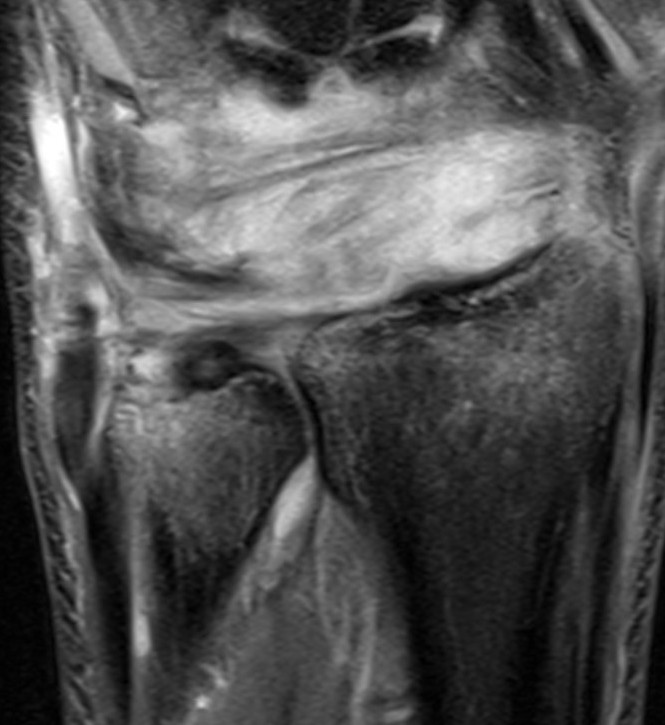

MRI demonstrating significant radiocarpal ligament disruption with radiocarpal instability under stress test